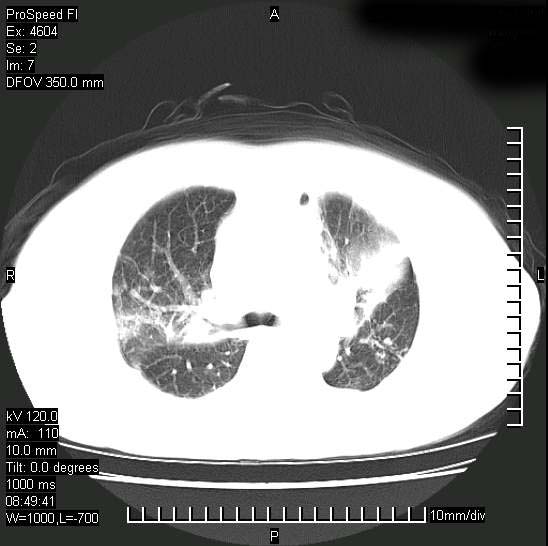

标题: CT15528:女性,79岁,近几日晚上高热,39度,仍咳少量血 [打印本页]

十几年前曾患肺结核,一周前突咳血约100ml,中性粒细胞稍高,诊断两上肺陈旧结核,下肺炎症,给予抗炎治疗,近几日晚上高热,39度,仍咳少量血,4天前ct及今天ct上传。

今天ct

短短几天内,病变范围明显增多扩大,以左侧明显,而且双侧出现胸水,还是考虑感染.

支持  结核ban感染,节段性肺不张,支气管内膜结核可能

短短几天内,病变范围明显增多扩大,以左侧明显,而且双侧出现胸水,我更多考虑左侧中心性肺癌并并阻塞性不张及肺炎,炎症变化也太快了!

继发性结核感染加重。左侧合并有支气管内膜结核。

无论是肿瘤还是炎症4天的时间都发展够快的,并且还在治疗中,如果说是左肺癌那么右肺的病变不好解释,本人更加倾向于炎症,左肺舌叶支气管被痰栓或血凝块堵塞,造成阻塞性肺炎。

1)两肺结核并感染。2)不排除左肺上叶中央型肺癌并阻塞性肺炎、肺不张可能;建议行纤支镜检查。3)右肺门及纵隔淋巴结肿大。4)双侧胸腔积液。

陈旧性肺结核及左下肺不张,咯血后肺部感染,双胸腔积液,高热可能与痰液引流不畅有关。